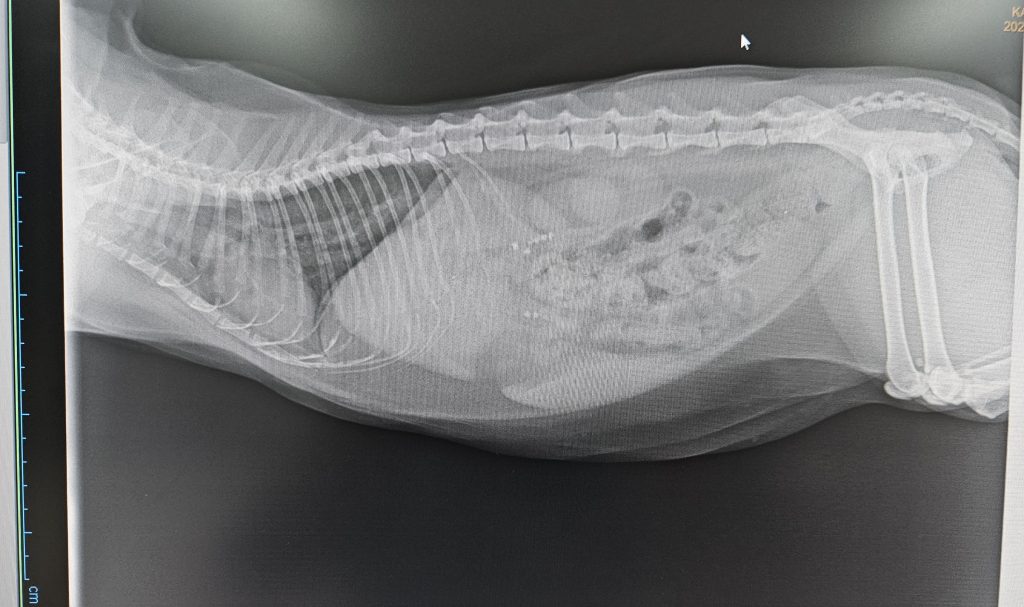

Die Erstellung von Röntgenbildern ist in der Tierarztpraxis eine unverzichtbare Untersuchungsmethode.

Die Röntgenbilder werden nicht mehr auf analogen Röntgenfilmen aufgenommen, sondern digital. Das digitale Röntgen liefert in wenigen Minuten Bilder in hervorragender  Bildqualität und kann anschließend, wenn nötig, auf dem Monitor nachbearbeitet werden.